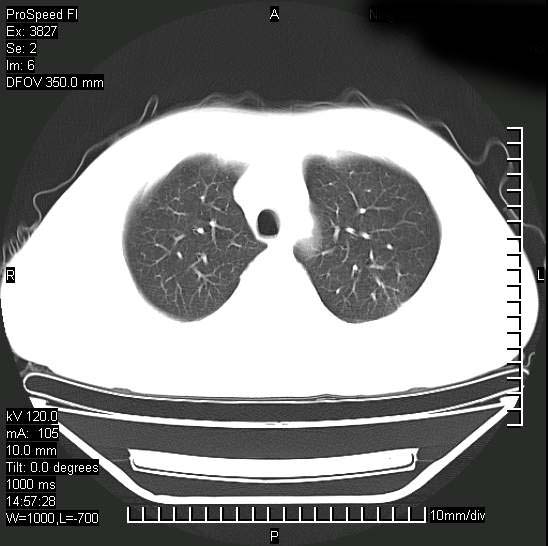

男性,一月前出现右侧肋区疼痛,较剧烈,干咳,无发热,自诉使用抗炎药后缓解,几天前又出现左侧剧烈疼痛,

发热,体温38。9,今天ct,考虑左侧包裹性脓胸,胸腔积液,右上中肺小斑片影,结核/炎症?胸水未见恶性细胞。

支持:脓胸!并双肺继发性肺结核!

脓胸!并双肺继发性肺结核!

左侧肺脓疡,化脓性胸膜炎(脓胸),不支持结核诊断,建议继续抗感染治疗

脓胸没问题,肺内还可见感染灶,感觉不像是结核性病变.